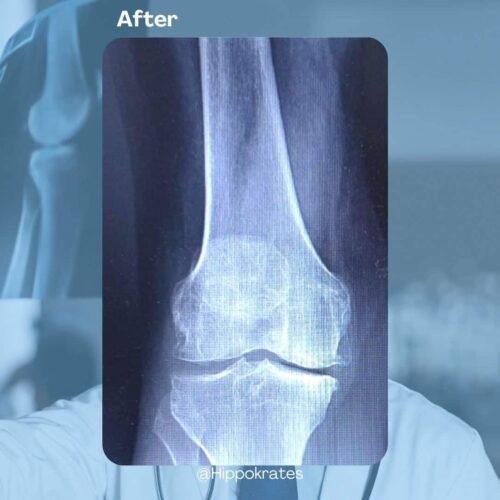

Il risultato, come possiamo vedere da questo PRIMA/DOPO è un sensibile miglioramento delle condizioni cliniche di pazienti affetti da osteoartrite e osteoporosi.